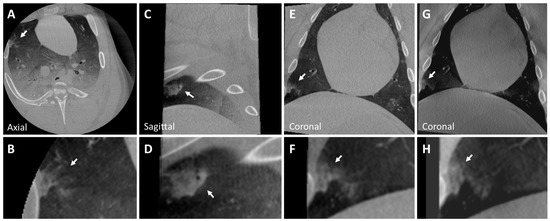

3.1. Ex Vivo Swine Lungs

| Diameter (mm) | CT Attenuation (HU) | |

|---|---|---|

| Lung Nodule | <30 | 50 (30) |

| Nodule 1 | 11 × 6.5 | |

| Nodule 2 | 8 × 7 | −360 (±55) |

| Nodule 3 | 10 × 9 | 25 (20) |

| Nodule 4 | 9 × 8 | −330 (50) |

| Nodule 5 | 16 × 12 | −310 ( |